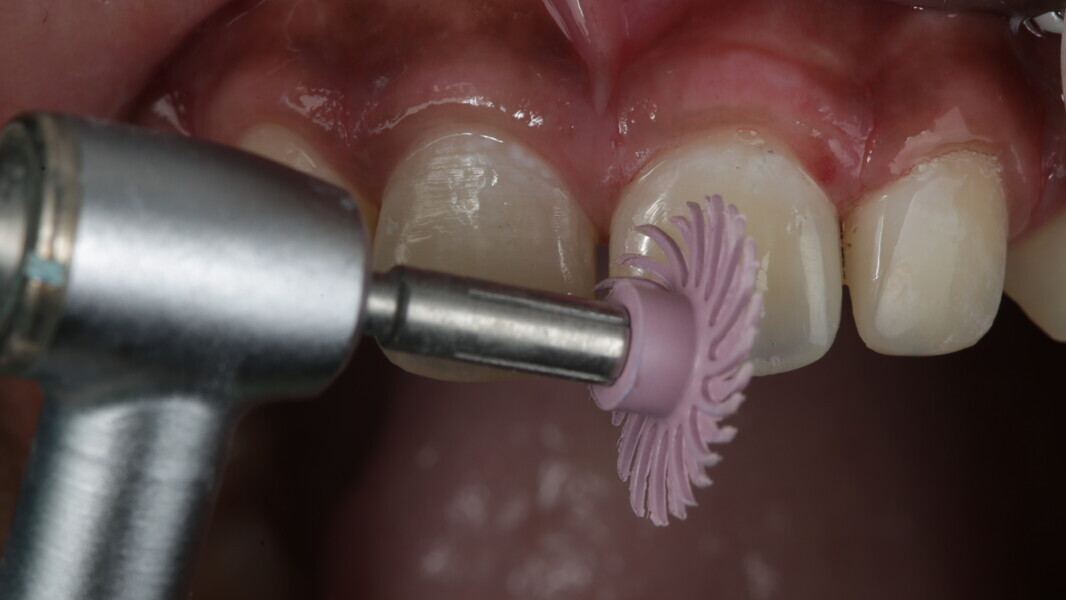

Fig 31-41: Polishing protocol and post-op